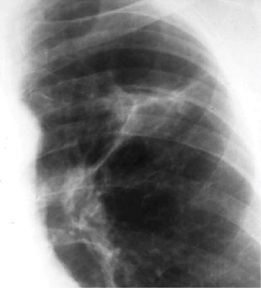

Comment on below CXR (in context of patient with TB)?

Ghon focus is a small round area of shadowing that results from granulomatous inflammation. Classically found in the midzone (upper part of lower lobe or lower part of upper lobe).

If the Ghon focus also involves infection of adjacent lymph nodes / hilar lymph nodes - it is known as Ghons complex (or primary complex) - seen in the photo.

When it undergoes fibrosis/calcify (as part of healing) - it is called Ranke complex.

In contrast, TB reactivation/re-infection - cavitation occur & there is no lymphadenopathy.